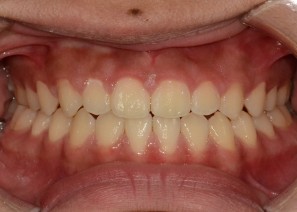

Before

After